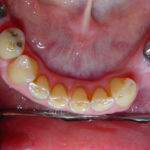

Case 6 – Upper Crowns / Lower Implants Makeover

- After